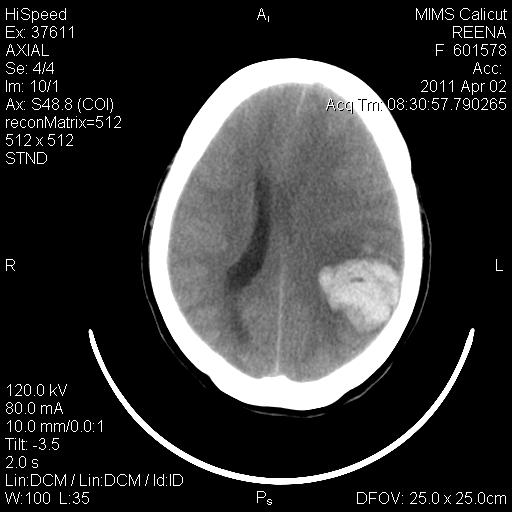

IMAGING-CT BRAIN

Left tempero parietal haematoma 4.1 cm x 3.5 cm with mass effect and midline shift of about 9 mm